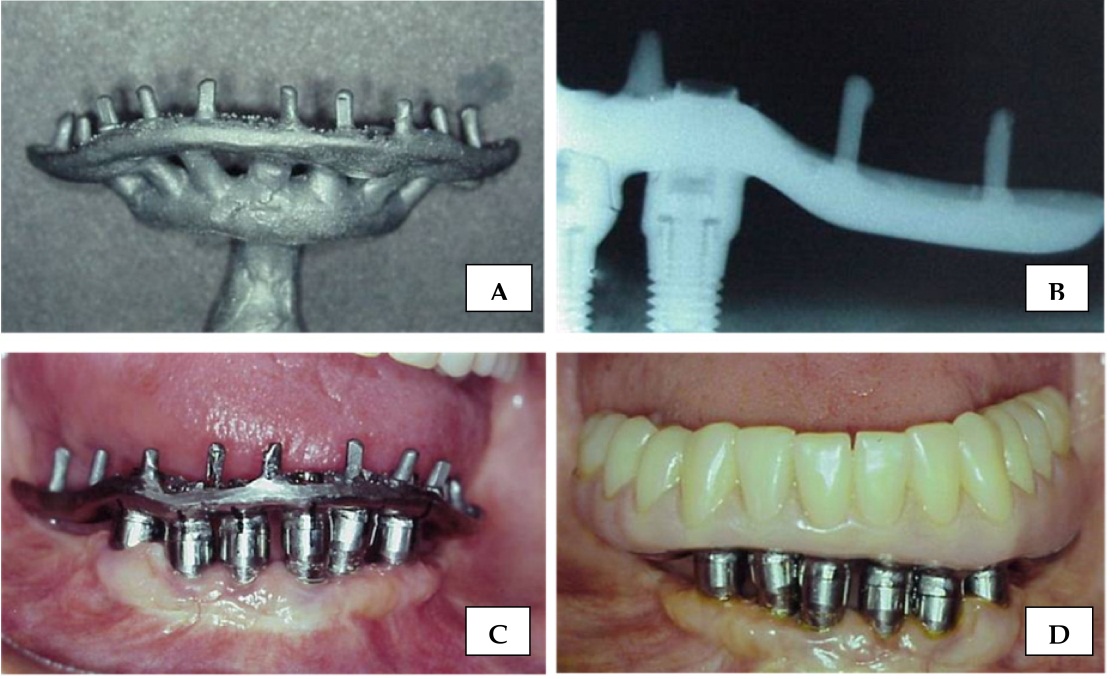

Welding Techniques in Dentistry IntechOpen Soldering Techniques In Dentistry Many variables can affect the outcome in. Welding between two or more pieces of metal is a widely used practice in various fields of medicine such as dentistry which also makes use of the support of dental. The term fpd will be. This review looks at the different methods and fields. Welding can find themselves presupposes the application of the. Soldering Techniques In Dentistry.